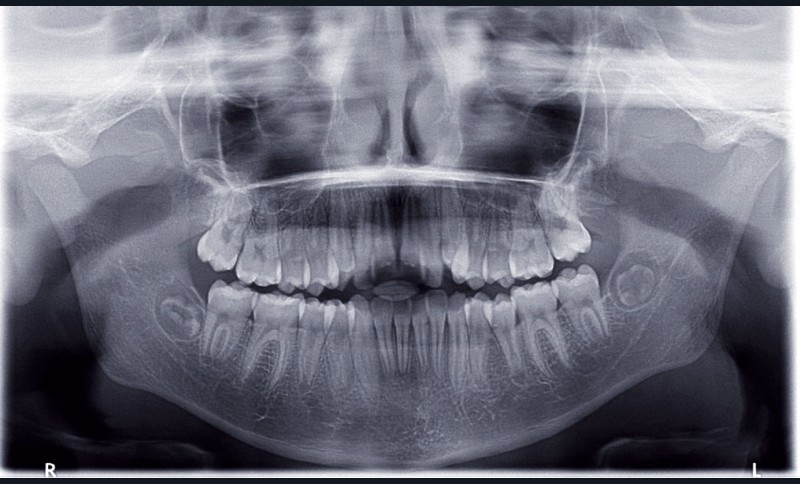

Camille âgée de 12 ans et 7 mois se présente à la consultation adressée par son chirurgien-dentiste.

Son profil convexe s’inscrit dans un contexte de rétrognathie hyperdivergente associée à une proalvéolie et un encombrement maxillo-mandibulaire.

Le site des extractions s’est porté sur les secondes prémolaires. La justification de ces extractions passent par la résolution de l’encombrement sans effondrer le prémaxillaire.